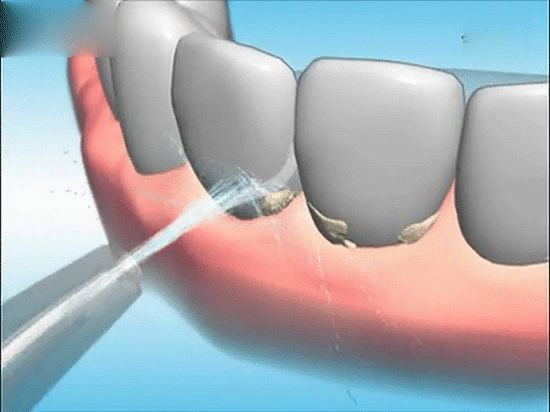

牙龈萎缩如果是病理性的则要通过正规的牙科医院来诊治,要积极的治疗牙周炎、牙龈炎,定期清理牙结石。针对使用假牙的人,如果假牙不适合,要提早的修整,定期的进行牙齿的保健。